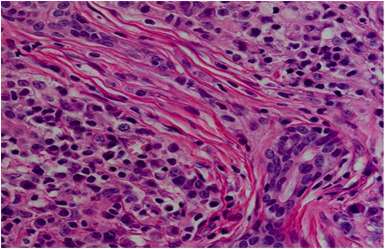

La enfermedad relacionada con la inmunoglobulina G4 (IgG4), conocida como "IgG4-related disease" en inglés, es un trastorno sistémico de causa desconocida que se caracteriza por una fibroinflamación altamente característica. Esta…